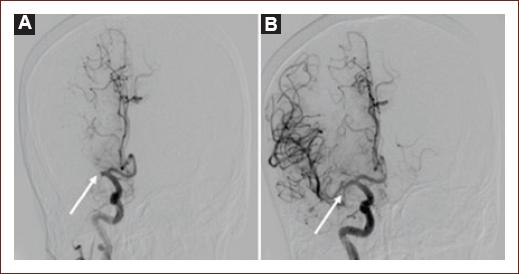

DSA

DSA is considered the gold standard to evaluate vessel morphology, level, and occlusion percentage. The thrombolysis in cerebral infarction (TICI) scale was developed for DSA studies with the objective of quantifying response to reperfusion therapies45; nowadays, a modified version (mTICI, Table 1) is used, which reflects the increasing use of MT46. DSA also allows us to evaluate collaterals using the American Society of Interventional and Therapeutic Neuroradiology/Society of interventional Radiology scale (Table 2), which is useful to characterize collaterals quality, with very important implications for clinical outcome47. The use of DSA (outside MT) in AIS is decreasing, although it is still used when in doubt, even after CTA or MRA43. Figure 6 shows a DSA before and after the retrieval of a thrombus that was occluding the proximal right MCA.